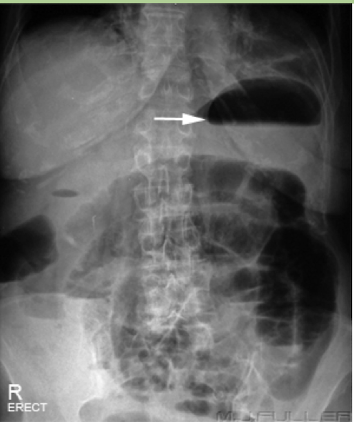

Pneumoperitonem

free air under the diaphragm

abnormal finding, perforated until proven otherwise

Abdominal Radiograph